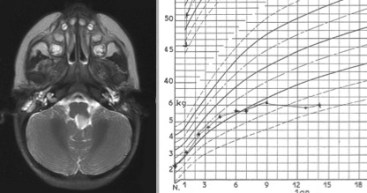

-

tumeur du V4 révélée par une anorexie du nourrisson avec stagnation pondérale les troubles neuro-endocriniens : puberté précoce ou au contraire impubérisme, retard staturo-pondéral